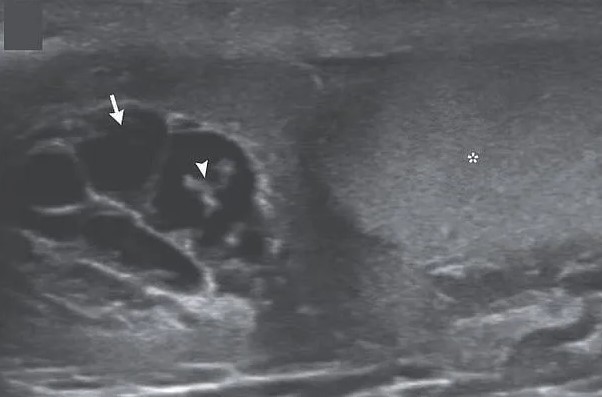

İngiliz Daily Mail gazetesinde yer alan habere göre, doktorlar hastanın skrotumunda hareket eden doğrusal yapılar keşfetti.

Nadir görülen enfeksiyon, New England Journal of Medicine tarafından yayınlanan bir vaka raporu ile ortaya çıktı. Hastayı muayene eden Max Süper Özel Hastanede kıdemli tıbbi danışman olan Dr. Amit Sahu, ultrasonda 'doğrusal yapıların hareket ettiğini' söyledi.

Sahu gözlemledikleri hareket eden doğrusal yapılar için 'dans edecen düzinelerce solucan' ifadesini kullandı. Sahu, 'Lenf sistemine göç ederek kanalların genişlemesine ve işlev bozukluğuna neden oldular' dedi.

Ultrasondan sonra doktorlar skrotumdan sıvı örneği aldı ve mikroskop altında inceledi.